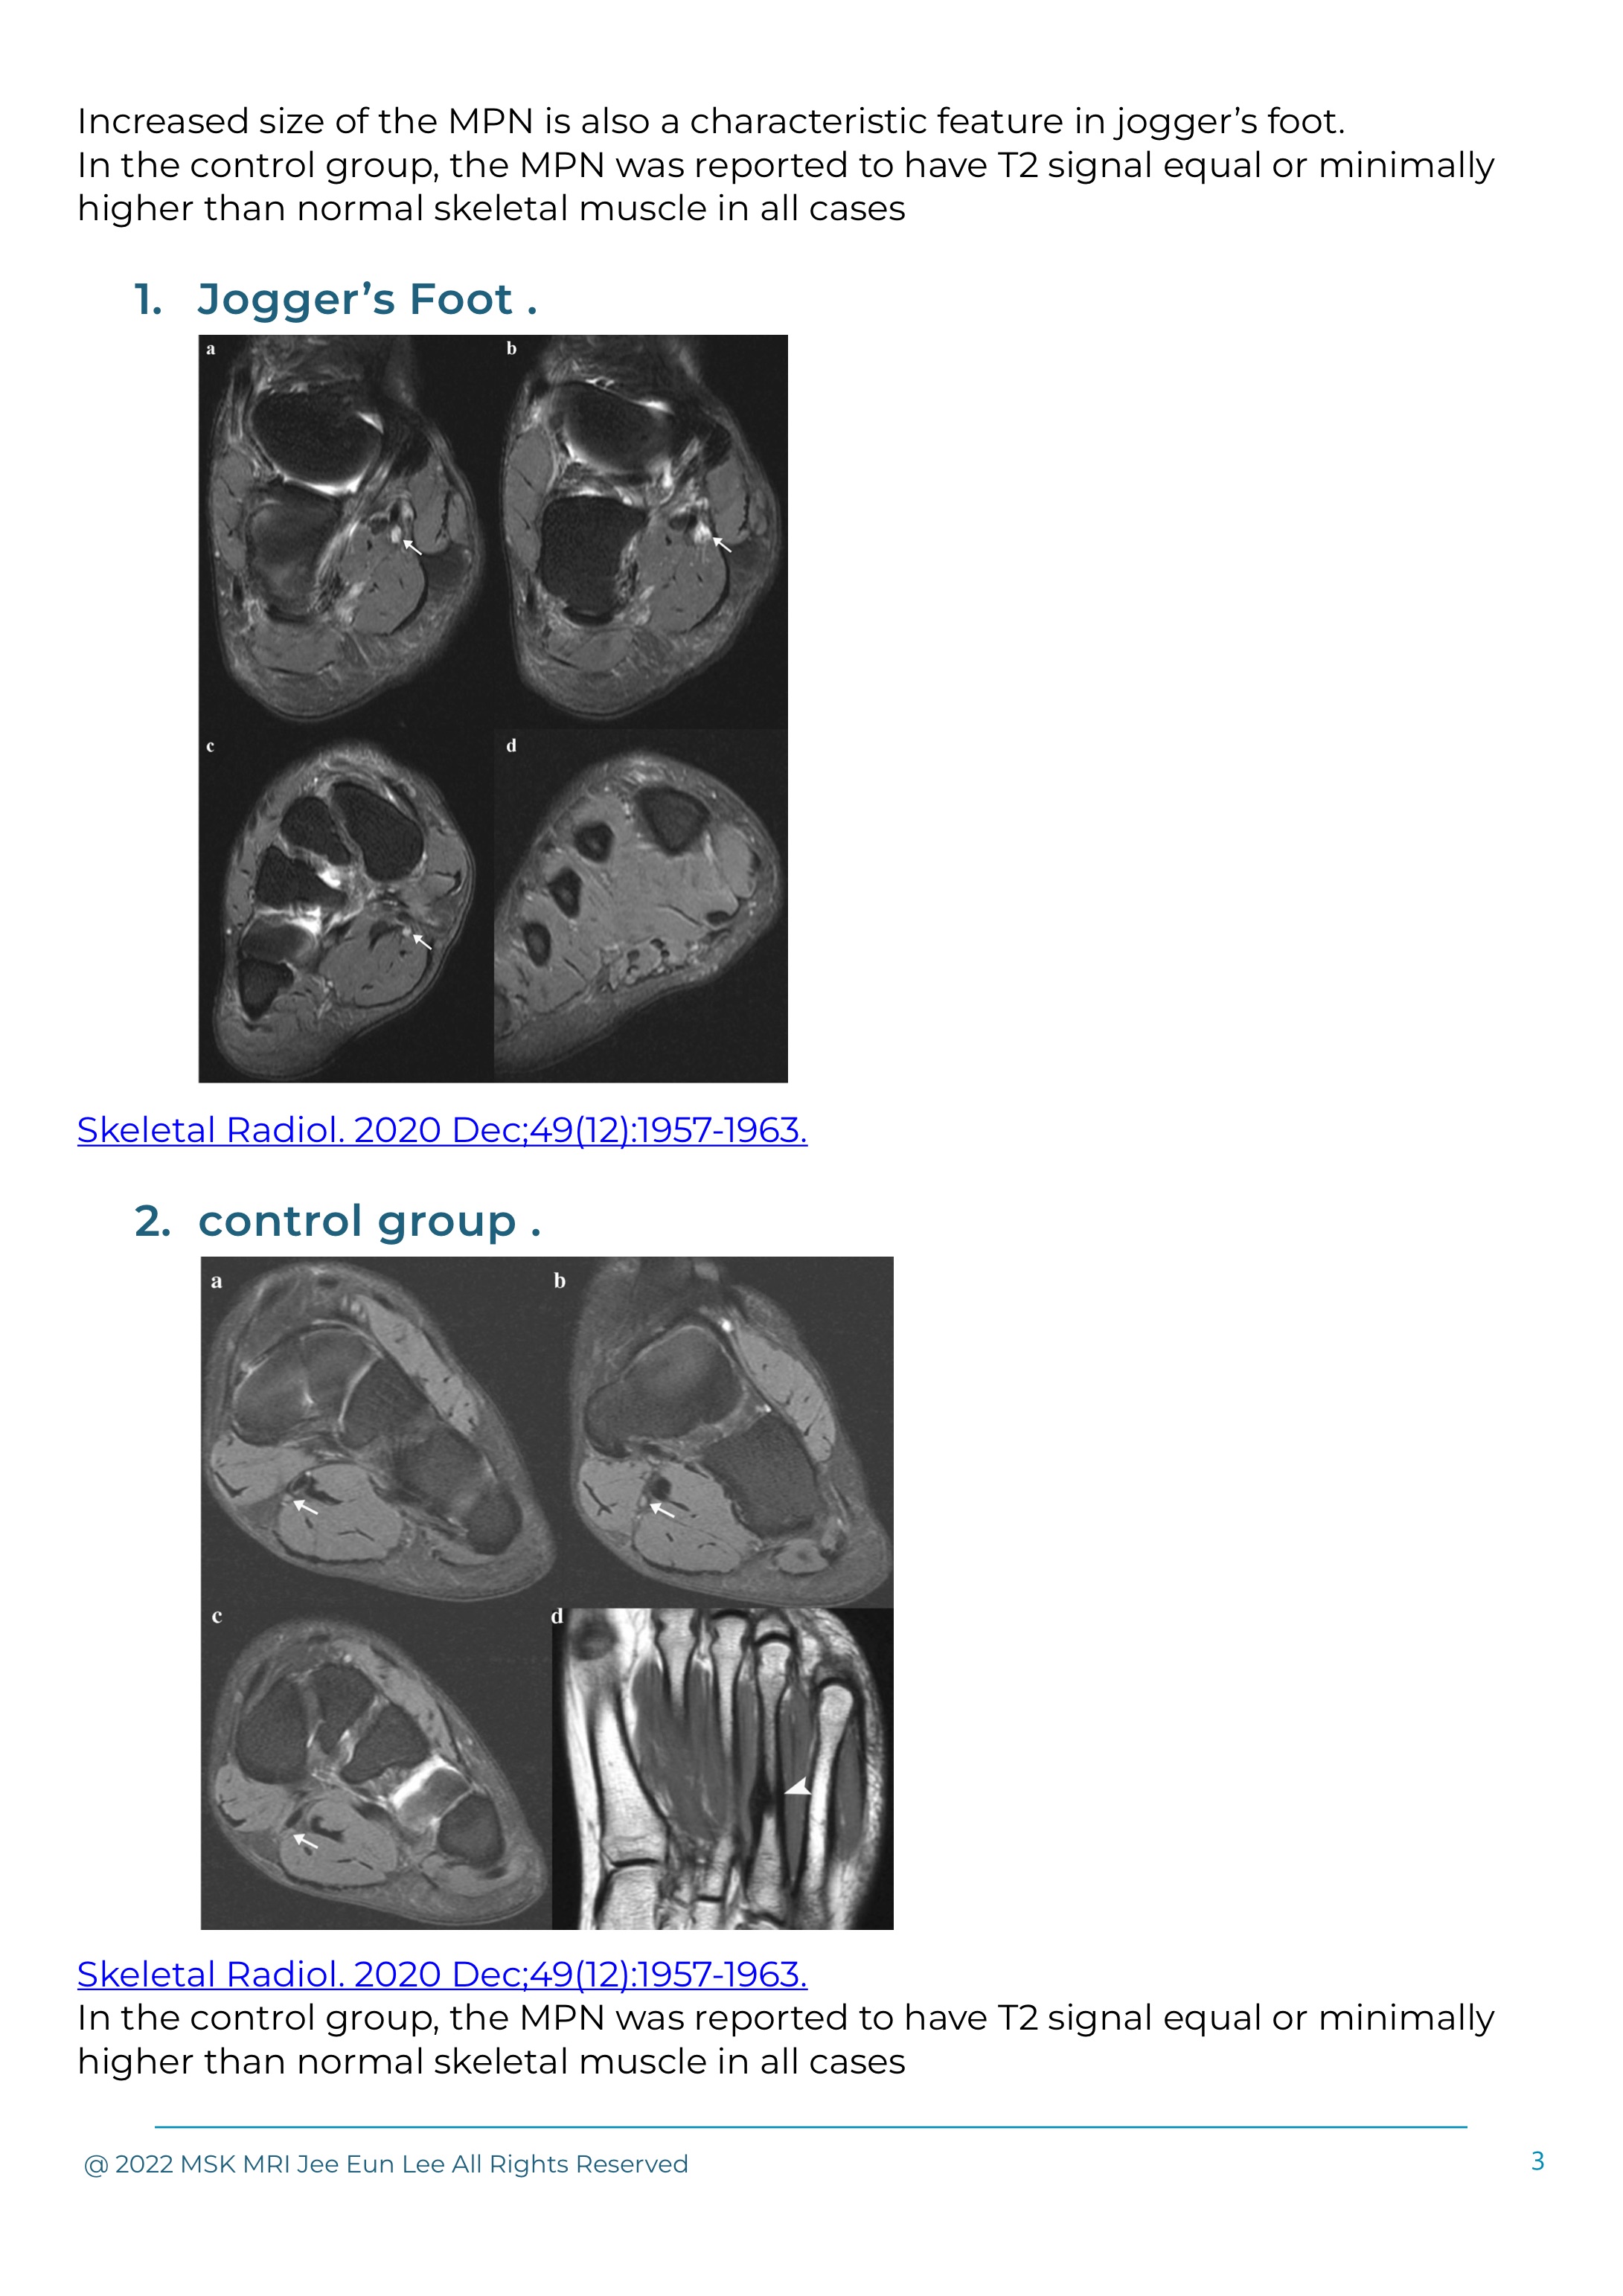

Abnormal T2 signal of the MPN is a key feature seen in positive jogger’s foot cases.

High signal intensity on T2-weighted images or fatty atrophy involving the abductor hallucis and flexor digitorum brevis muscles is indicative of medial plantar nerve entrapment at the ankle.